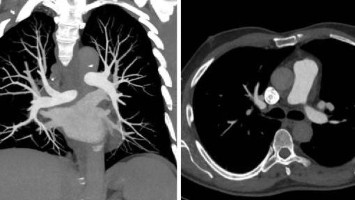

Lungenembolie mit weniger Bildgebung sicher ausschließen

Der seit Jahren zunehmende Einsatz der CT-Pulmonalisangiografie (CTPA) korreliert nicht mit der Entdeckung klinisch relevanter Lungenembolien. Französische Notärztinnen und -ärzte plädieren deswegen für einen neuen Diagnosealgorithmus, mit dem sich bildgebende Untersuchungen einsparen lassen, ohne die Sicherheit der Patienten zu gefährden.